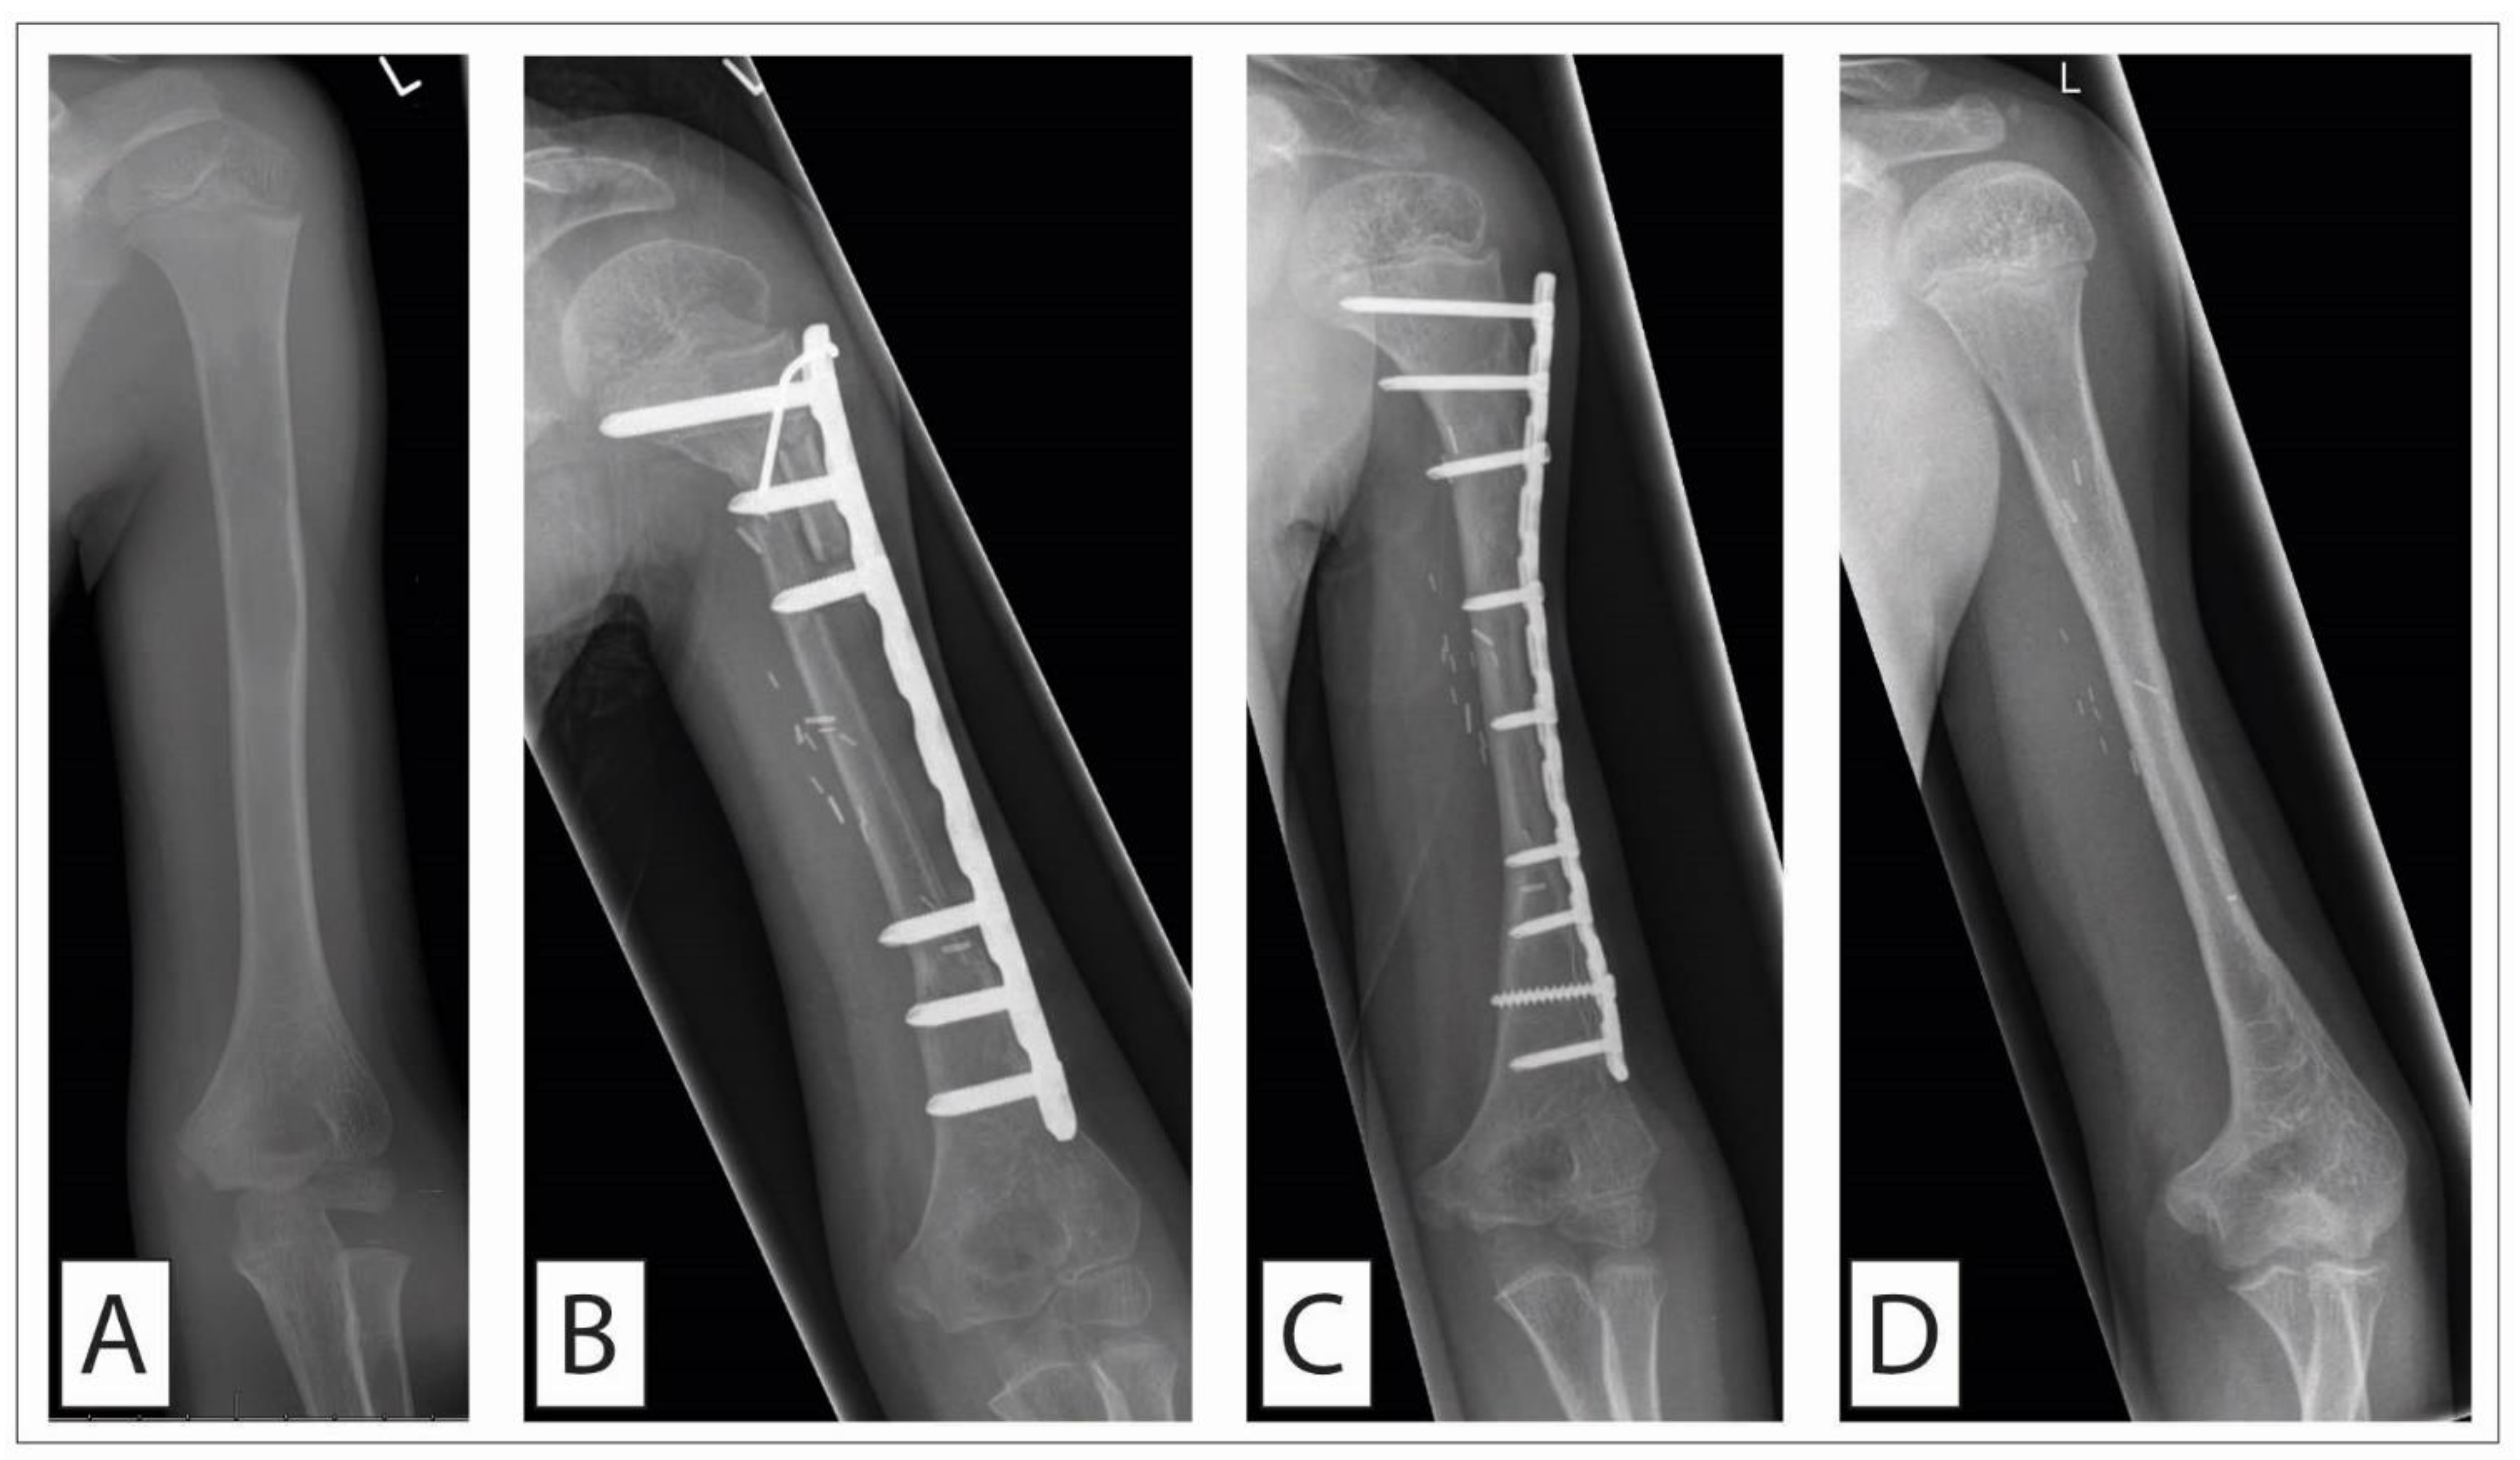

2.2.4. Expandable Prostheses

The alternative for rotationplasty in children with malignant bone sarcoma around the knee is the implantation of an expandable prosthesis that can accommodate for the still expected increase in leg length. Portney et al. [48] published a meta-analysis on the outcome of expandable prostheses for primary bone malignancies in skeletally immature patients including 28 retrospective studies. All studies were of level IV evidence (case series and retrospective studies). In total, 292 cases of individual patient data sets were available from the 634 patients analyzed. Mean age in this subpopulation was 10.1 years at the time of surgery; mean follow-up was 67 months. The main tumor site was the distal femur (216 patients, 74%). Musculoskeletal Tumor Society scores averaged 80.3. Overall mortality was 22%. Several lengthening procedures had to be performed in patients with expandable distal femur replacements (average, 4.4; mean lengthening distance, 43 mm). The overall complication and revision rate was 43%, increasing to 59% in patients with 5 to 10 years of follow-up, and 89% in patients with >10 years of follow-up. Improved outcome results and lower failure rates have, however, been reported with newer generations of expandable prostheses [49]. In this study, the Phenix-Repiphysis system that was used from 1994 to 2008 was compared with the Stanmore JTS non-invasive prosthesis that was used from 2008 to 2016. Functional results were significantly better in the Stanmore group. Patients treated with this device presented with a mean knee flexion of 112 ± 38° and a Musculoskeletal Tumor Society score of 87.6 ± 5.4. With respect to implant survival, the Stanmore group also vastly outperformed the Phenix-Repiphysis system: At the end of follow-up all Stanmore implants were still in place while all Phenix-Repiphysis devices had already been explanted again. Limb length equality was obtained in 79% patients with the Phenix-Repiphysis system and in 84% with the Stanmore implant. Additionally, Windhager et al. [50] state, in their review, satisfactory functional results with an averaged Musculoskeletal Tumor Society score of 78.3 but a high complication rate of 27.3% of infections and 22.4% of mechanical failure. It is this high complication rate that prompts some authors to still argue in favor of rotationplasty [51]. In patients who have almost reached their full body height, the defect resulting from tumor resection is, however, usually treated by the implantation of a regular megaprosthesis (Figure 2). In a case in which the complete knee joint has to be removed in toto, reconstruction of the extensor mechanism can be challenging. Several techniques have been suggested to address this problem, for example, using the gastrocnemius aponeurosis as an augment for the extensor mechanism [52]. One interesting technique is an extraarticular knee resection with preservation of the quadriceps and patella tendon [53,54].